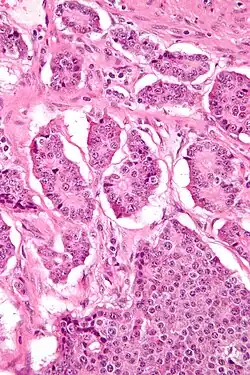

| Micrograph of a neuroendocrine tumor. H&E stain. | |

Neuroendocrine tumors (NETs) are neoplasms that arise from cells of the endocrine (hormonal) and nervous systems. They most commonly occur in the intestine, where they are often called carcinoid tumors, but they are also found in the pancreas, lung, and the rest of the body.

Although there are many kinds of NETs, they are treated as a group of tissue because the cells of these neoplasms share common features, including a similar histological appearance, having special secretory granules, and often producing biogenic amines and polypeptide hormones.[1]

NETs are often small, yellow or tan masses, often located in the submucosa or more deeply intramurally, and they can be very firm due to an accompanying intense desmoplastic reaction. The overlying mucosa may be either intact or ulcerated. Some GEP-NETs invade deeply to involve the mesentery.[72] Histologically, NETs are an example of "small blue cell tumors," showing uniform cells which have a round to oval stippled nucleus and scant, pink granular cytoplasm. The cells may align variously in islands, glands or sheets. High power examination shows bland cytopathology. Electron microscopy can identify secretory granules. There is usually minimal pleomorphism but less commonly there can be anaplasia, mitotic activity, and necrosis.